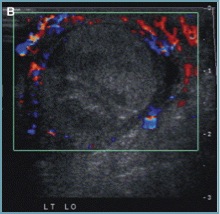

Testicle torsion will have absence of testicular flow and may get to the poibnt of hyperemia surrounding the testicle: